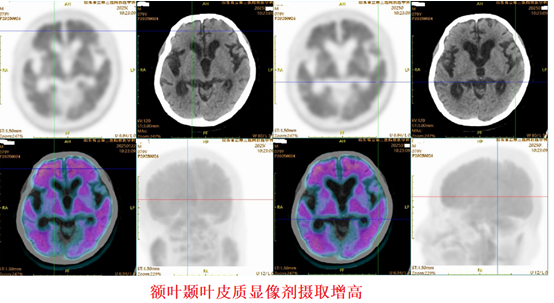

神经内科主任赵修敏、副主任刘磊接诊患者后,通过体格、神经心理学量表、脑脊液标记物等检查,对患者病情进行详细评估,并联合核医学科刘坚主任团队,为其进行了临床氟[¹⁸F]贝他苯PET脑显像。这项检查可提前15-20年早期精准诊断阿尔茨海默病,从而实现该病的早期诊断、干预、治疗。另外,随着阿尔茨海默病治疗技术的不断发展,大量治疗后患者也迫切需要通过该检查进行后期疗效评估及随访。这也是山东省立第三医院开展的我省首例氟[¹⁸F]贝他苯脑PET脑显像检查。经过检查,细致判读并确认β淀粉样蛋白(Aβ)显像阳性,明确了患者重度阿尔茨海默病的诊断。

显像结果:β淀粉样蛋白显像阳性

赵修敏主任向患者家属解释,β淀粉样蛋白作为阿尔茨海默病致病元凶之一,其在大脑中的异常沉积被认为是阿尔茨海默病病理的始发和核心事件,且在脑内的异常沉积程度与病情进展程度高度相关。